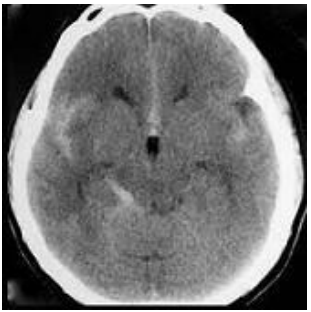

Homem, 70 anos vítima de queda do telhado (3 metros de altura) com trauma craniano seguido de perda da consciência no local. Trazido pelo Serviço de Atendimento Médico de Urgência (SAMU) à sala de trauma de hospital terciário. Admitido pela equipe do trauma em Glasgow 10, anisocoria com pupila esquerda maior que direita. Frente o quadro do paciente e a tomografia de crânio abaixo (figura 4), assinale a alternativa que contenha a conduta correta a ser tomada.

Figura 4 tomografia de crânio sem contraste

Provas